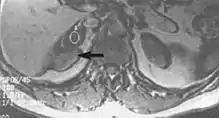

Metal artifacts

Metal artifacts occur at interfaces of tissues with different magnetic susceptibilities, which cause local magnetic fields to distort the external magnetic field. This distortion changes the precession frequency in the tissue leading to spatial mismapping of information. The degree of distortion depends on the type of metal (stainless steel having a greater distorting effect than titanium alloy), the type of interface (most striking effect at soft tissue-metal interfaces), pulse sequence and imaging parameters. Metal artifacts are caused by external ferromagnetics such as cobalt containing make-up, internal ferromagnetics such as surgical clips, spinal hardware and other orthopaedic devices, and in some cases, metallic objects swallowed by people with pica.[3] Manifestation of these artifacts is variable, including total signal loss, peripheral high signal and image distortion (Figs 3 and 4).[1]